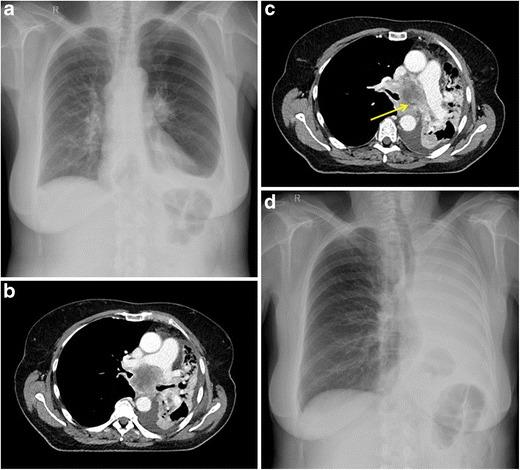

Lung cancer patients often experience potentially life-threatening medical urgencies and emergencies, which may be a direct or indirect result of the underlying malignancy. This pictorial review addresses the most common thoracic, neurological and musculoskeletal medical emergencies in lung cancer patients, including superior vena cava syndrome, pulmonary embolism, spontaneous pneumothorax, cardiac tamponade, massive haemoptysis, central airway obstruction, oesophagorespiratory fistula, malignant spinal cord compression, carcinomatous meningitis, cerebral herniation and pathological fracture. Emphasis is placed on imaging findings, the role of different imaging techniques and a brief discussion of epidemiology, pathophysiology and therapeutic options. Since early diagnosis is important for adequate patient management and prognosis, radiologists have a crucial role in recognising and communicating these urgencies and emergencies.

肺癌患者常经历可能危及生命的医学急症,这可能是潜在恶性肿瘤的直接或间接结果。本图像综述探讨了肺癌患者最常见的胸部、神经和肌肉骨骼医学急症,包括上腔静脉综合征、肺栓塞、自发性气胸、心脏压塞、大量咯血、中央气道阻塞、食管气管瘘、恶性脊髓压迫、癌性脑膜炎、脑疝和病理性骨折。重点介绍影像学表现、不同成像技术的作用,并简要讨论流行病学、病理生理学和治疗选择。由于早期诊断对患者的充分管理和预后很重要,放射科医生在识别和传达这些急症方面起着关键作用。